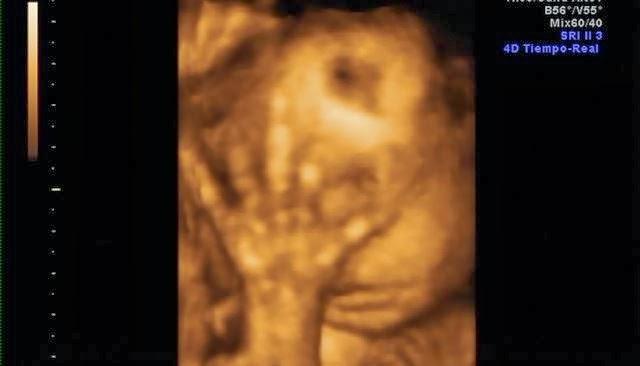

La parte positiva es que lo ví una vez extra por la seguridad social.. jejje y las fotos que me dieron son muy monas.

Su carita!Y estas son algunas capturas de pantalla de la eco 4d que me hice a principios de mes. Que ya de paso decir, que esta no me gustó NADA!! Tuvimos que esperar 2 horas para que nos cogieran, la eco nos la hicieron con prisas, y sólo se le vió la mitad de la cara.. así que para habernos gastado 100€ muy mal!! No os recomiendo la Ginecóloga de Gandia, Dra.Escrivá.